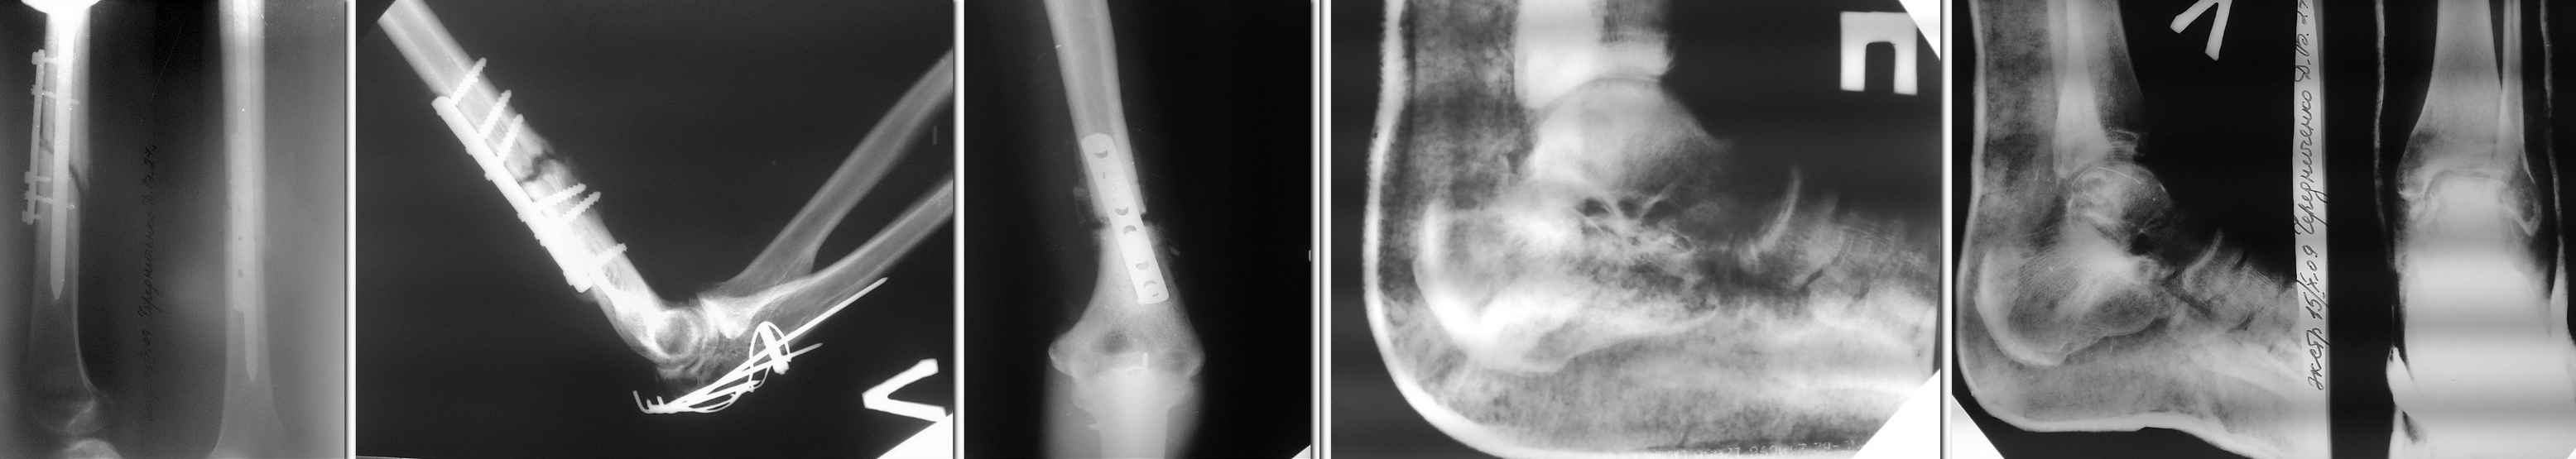

Уважаемые коллеги! Будем признательны любому совету в отношении тактики лечения пациента Ч. 27 лет, поступившего в наше отделение для этапного лечения по поводу сочетанной травмы, полученной 19.07.2009 в ДТП.

Оперирован в другом лечебном учреждение 05.08.09- остеосинтез левой бедренной кости, левой плечевой кости, левого локтевого отростка, трансартикулярная фиксация спицами левой таранной кости, выполнена закрытая репозиция перелома правой пяточной кости гипсовым лангетом. В настоящее время признаки консолидации левой бедренной и левой плечевой костей выражены слабо, имеются контрактуры левых локтевого и коленного суставов, спицы удалены продолжается иммобилизация стоп. Мнения коллег по дальнейшей тактике лечения разошлись: - выполнить реостеосинтез бедренной и плечевой костей; - продолжать консервативное лечение в надежде на консолидацию переломов, поскольку оперативное пособие не приведёт к более ранней активизации больного из-за имеющихся переломов костей стоп и верхней конечности. Заранее спасибо.